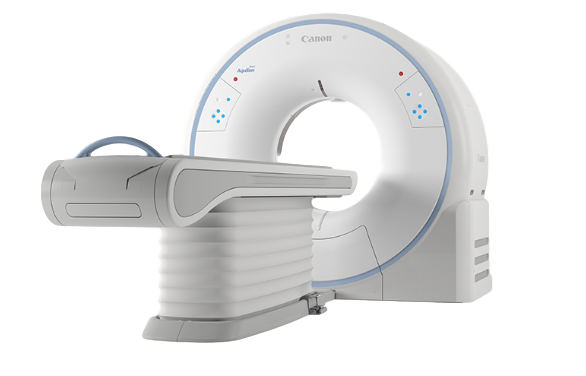

Начните с высоких технологий

Независимо от того, начинаете ли вы новый бизнес по созданию изображений, ищете надежную рабочую лошадку для эффективной обработки растущих рабочих нагрузок или расширяете устоявшийся бизнес по созданию изображений, Aquilion Start — это система КТ, подходящая для всех ваших повседневных потребностей в области обработки изображений.

Aquilion Start оснащен первоклассной технологией, изначально разработанной для высококачественных систем КТ. Он тщательно разработан и адаптирован к изменяющимся требованиям организаций здравоохранения, включая необходимость ускорения рабочих процессов, универсального доступа и разумной экономики.

Оптимизируйте производительность безопасно

Удобный для пациента дизайн Aquilion Start не только повышает эффективность, но и обеспечивает безопасность пациентов, помогая снизить нагрузку на медицинский персонал.

Как начинающие технологи, так и опытные специалисты могут по достоинству оценить интегрированные решения Aquilion Start, которые облегчают выполнение даже самых сложных задач.

Новый, улучшенный гентри — упакован по технологии

Гентри Aquilion Start включает в себя инновационные разработки, которые улучшают качество сканирования пациентов и обеспечивают отличную работоспособность и безопасность.

Просторное отверстие шириной 78 см и кушетка шириной 47 см позволяют комфортно сканировать даже самых крупных пациентов. Кушетка может быть опущена до минимальной высоты 31,2 см, что облегчает перенос пациентов с инвалидной коляски.